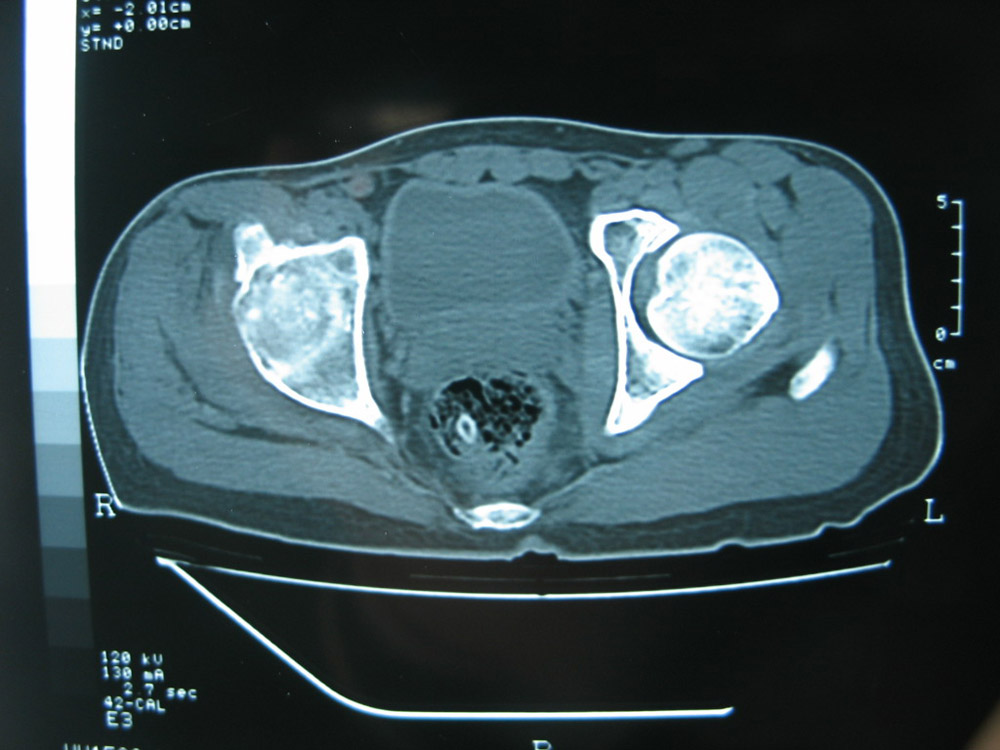

以下是引用卜一在2007-1-25 16:33:00的发言:[br]右侧髋关节股骨头及髋臼骨骨小梁疏松 粗糟,股骨头外形毛糟,软组织似肿胀,间隙略变窄.考虑:1 髋关节结核可能性大.2 缺血性坏死?3 化脓性髋关节炎?

以下是引用hhcckk在2007-1-25 17:18:00的发言:[br][br]支持髋关节结核,[br]依据关节面破坏,有脓肿,脓腔内有钙化,关节周围增生不明显,鉴别[br]1化脓性的病变增生明显,临床上有高热[br]2创伤引起的关节炎,无菌坏死不会引起关节面的破坏,而且不会在这么短的时间内出现[br]